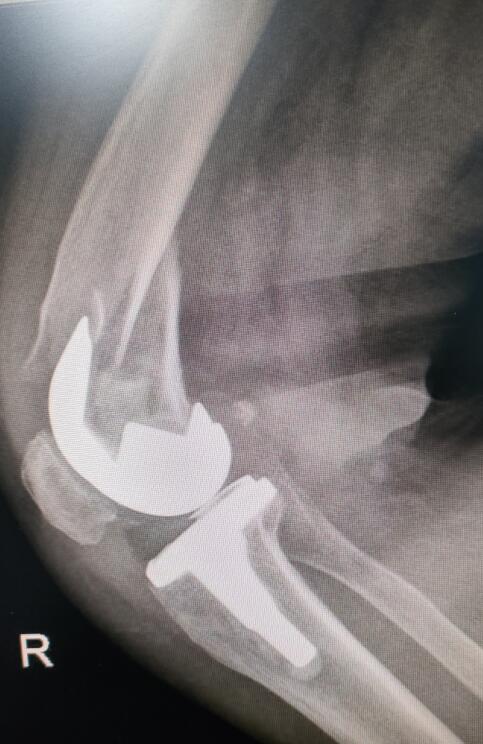

手术前照片

手术后照片